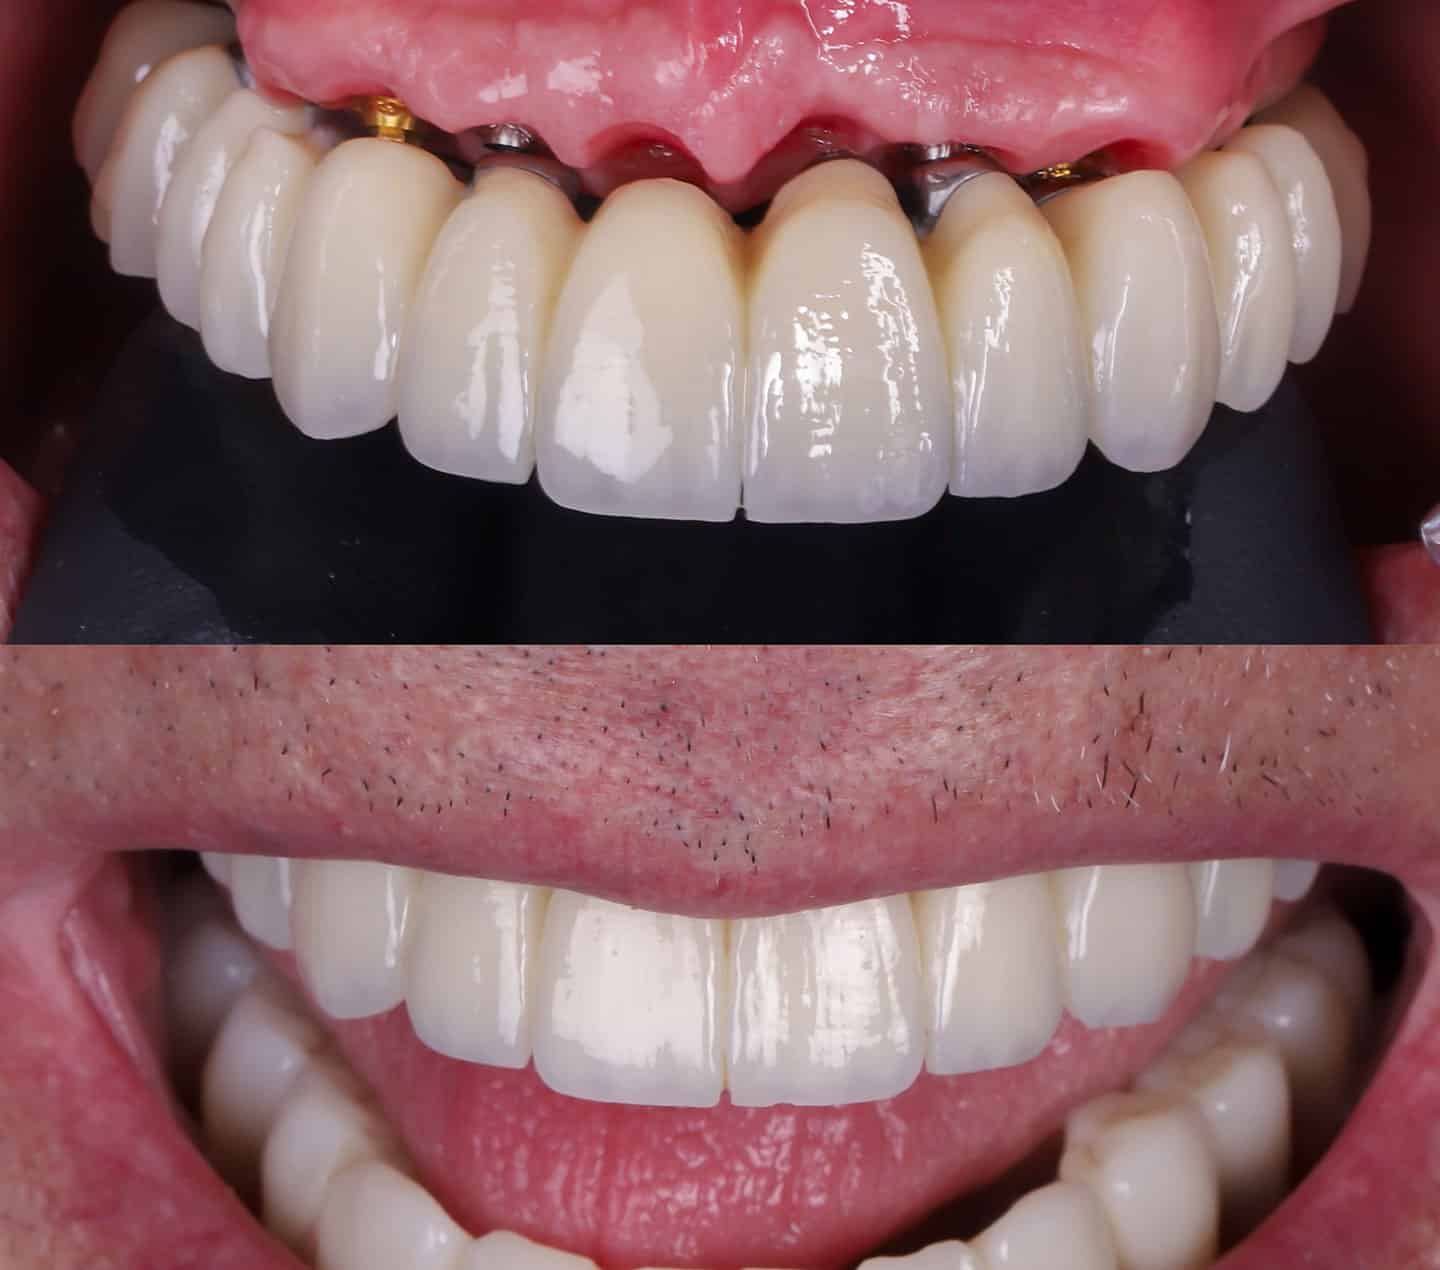

- Enfoque en la estética dental: No solo nos preocupa la funcionalidad. Como expertos en estética dental, diseñamos coronas que se mimetizan con el color, forma y brillo de tus dientes naturales.

4. Colocación de la corona definitiva

Una vez integrado, tomamos moldes precisos para fabricar la corona de cerámica o circonio. Esta pieza es la que dará el aspecto final de diente natural a tu sonrisa.